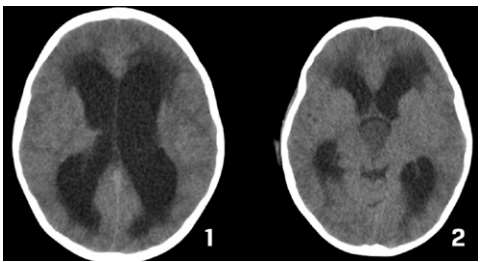

Caso clínico 3 para as questões 27 e 28.

Criança feminina, 04 anos, é encaminhada de Unidade de Pronto Atendimento (UPA) de Olinda-PE com história de cefaleia acompanhada de vômitos, inapetência e sonolência há 03 dias, sendo solicitado parecer da neurocirurgia. Ao exame: ECG Pediátrica de 13 (Resposta Ocular = 3 + Resposta Verbal = 4 + Resposta Motora = 6), isocórica e RFM lentificado bilateralmente, mobilizando todos os membros e reflexos presentes e simétricos.

Seguem, abaixo, as imagens de TC de crânio sem e com contraste da paciente, com índice de Evans de 0,41.

Pelas imagens mostradas, qual o mais provável diagnóstico e o objetivo do tratamento para a paciente?

Caso clínico 3 para as questões 27 e 28.

Criança feminina, 04 anos, é encaminhada de Unidade de Pronto Atendimento (UPA) de Olinda-PE com história de cefaleia acompanhada de vômitos, inapetência e sonolência há 03 dias, sendo solicitado parecer da neurocirurgia. Ao exame: ECG Pediátrica de 13 (Resposta Ocular = 3 + Resposta Verbal = 4 + Resposta Motora = 6), isocórica e RFM lentificado bilateralmente, mobilizando todos os membros e reflexos presentes e simétricos.

Seguem, abaixo, as imagens de TC de crânio sem e com contraste da paciente, com índice de Evans de 0,41.

Como se calcula o índice de Evans que foi de 0,41 e o que se fazer pela urgência nesse caso, respectivamente?